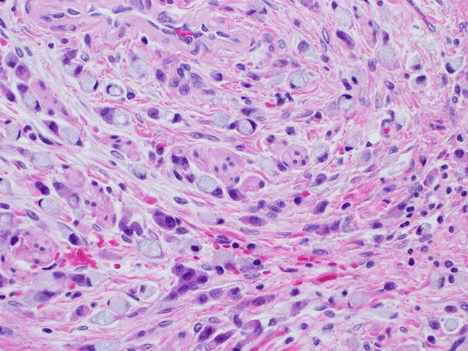

Microscopic examination of the uterus exhibited areas of both low-grade and high-grade sarcoma (Figure 2). Focal vascular invasion by low grade tumor was identified. The tumor appeared to extend to the cervical margin. Immunostains were performed on the uterine tissue. The low-grade tumor cells were positive for CD10 and negative for Caldesmon. In the high-grade tumor area, CD10 expression was diminished with patchy Cyclin D1 positivity and focally positive areas of Caldesmon. A focus of leiomyoma was also noted.

Figure 2: Uterine sarcoma tissue at 40x.

The top image illustrates high grade uterine sarcoma with H&E staining. High grade cancer tissue stained positive for marker CD 10 (bottom left) and Cyclin D (bottom right). View Figure 2